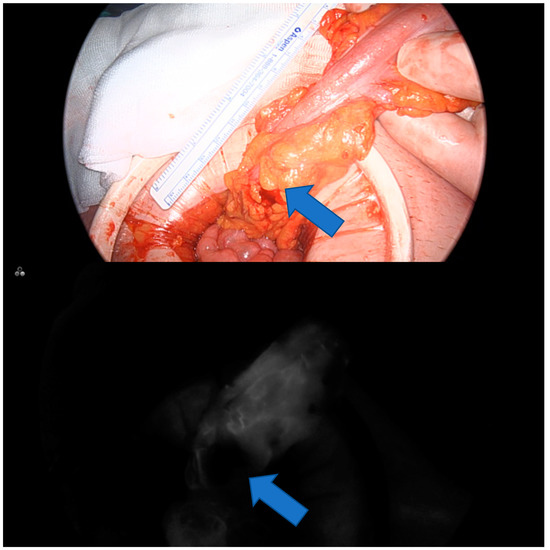

:1. Introduction